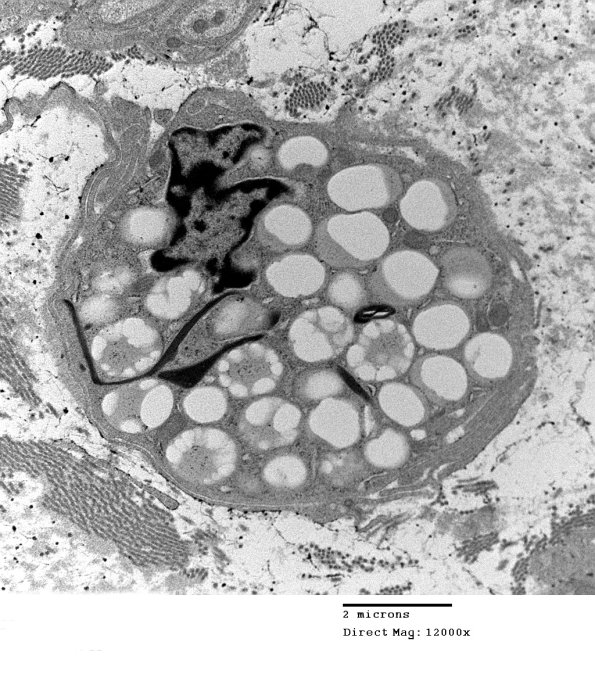

An additional migrating macrophage with lipidic debris.